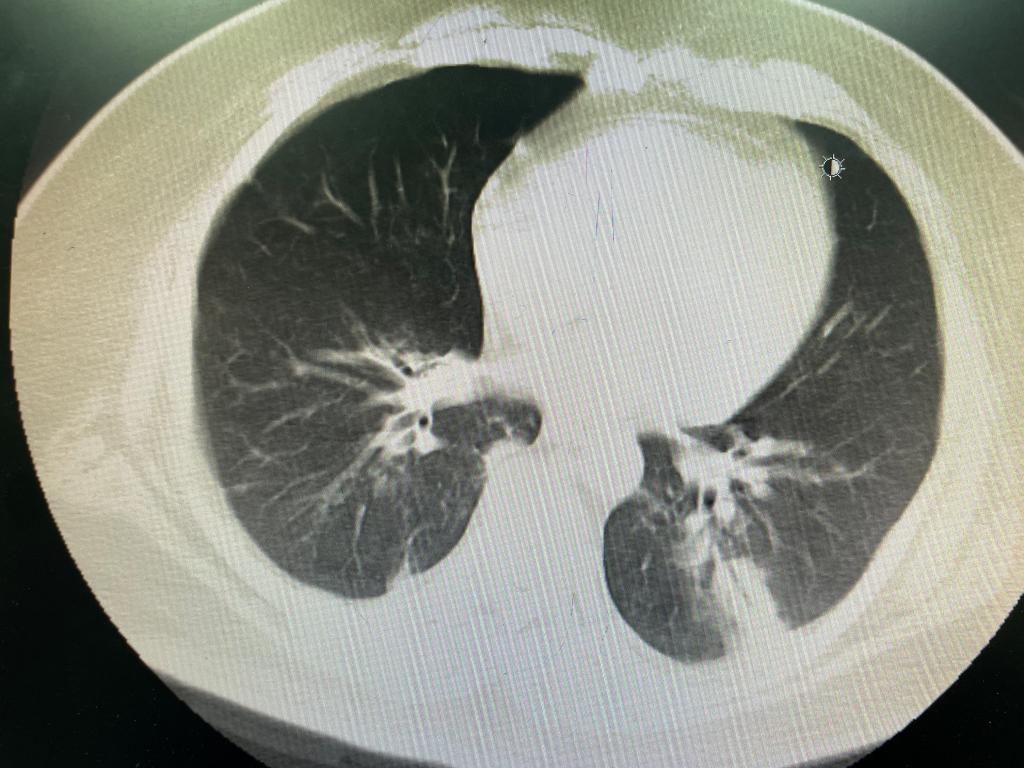

原发病发面,裴红红主任领导的团队第一时间确诊了腺病毒感染,机械通气方面以呼吸力学监测为指导,个体化调整呼吸机的参数,为患者提供了最佳的呼吸支持,做出对“肺休息”及肺部病变的动态评估;面对整个治疗过程中凝血与抗凝的监测和抗凝相关的消化道出血,团队也制定了综合的管理策略,确保患者的生命体征稳定。凭借有效的团队决策、丰富的临床经验及精心的治疗,经过10天ECMO支持,后续经皮气管切开有创通气、续贯高流量吸氧,顺利脱离呼吸机,改为鼻导管吸氧,患者成功转入普通病房。这一成功案例再次证明了ECMO在救治危重症患者中的重要作用,也展现了急诊科团队在应用这一技术方面的专业实力。

图5 ECMO下机后复查CT